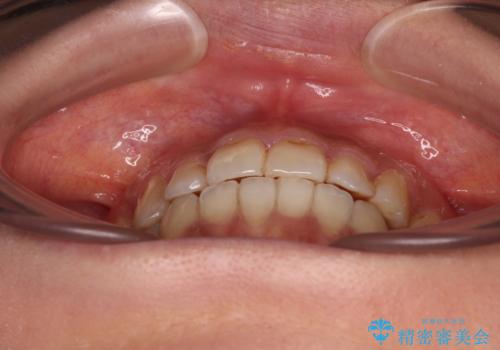

前歯のデコボコとクロスバイト インビザラインによる矯正治療

- 上下のクロスバイトと前歯のデコボコを気にして来院された患者様です。

骨格的に下顎がやや前方にあり、奥歯にクラウンが装着されているため、矯正治療後半の不安定な咬み合わせを避けるのであればワイヤー矯正がおすすめとなりますが、希望によりインビザラインにて治療を行うこととしました。

インビザラインを用い、IPR(歯と歯の間を削る)と歯列全体を拡大させることで、歯並びを整えていくこととしました。

懸念されたとおり、右下のクラウン部分が全く咬み合わず、仕上げの段階で治療期間が長くなりました。